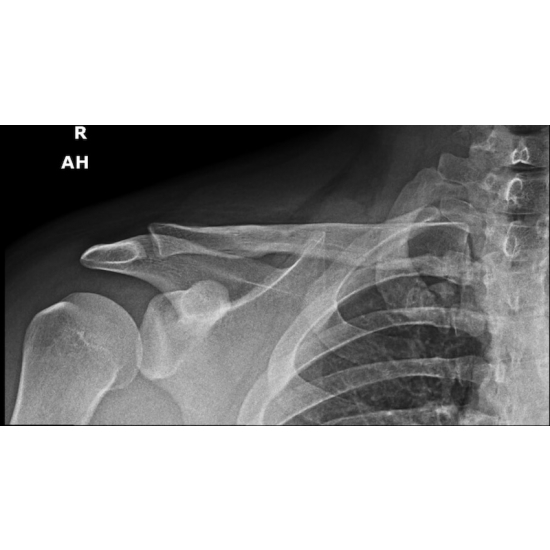

| Battered And Bruised: A Rare Cause Of Thoracic Pain In A Division One Offensive Lineman - Page #3 | |||